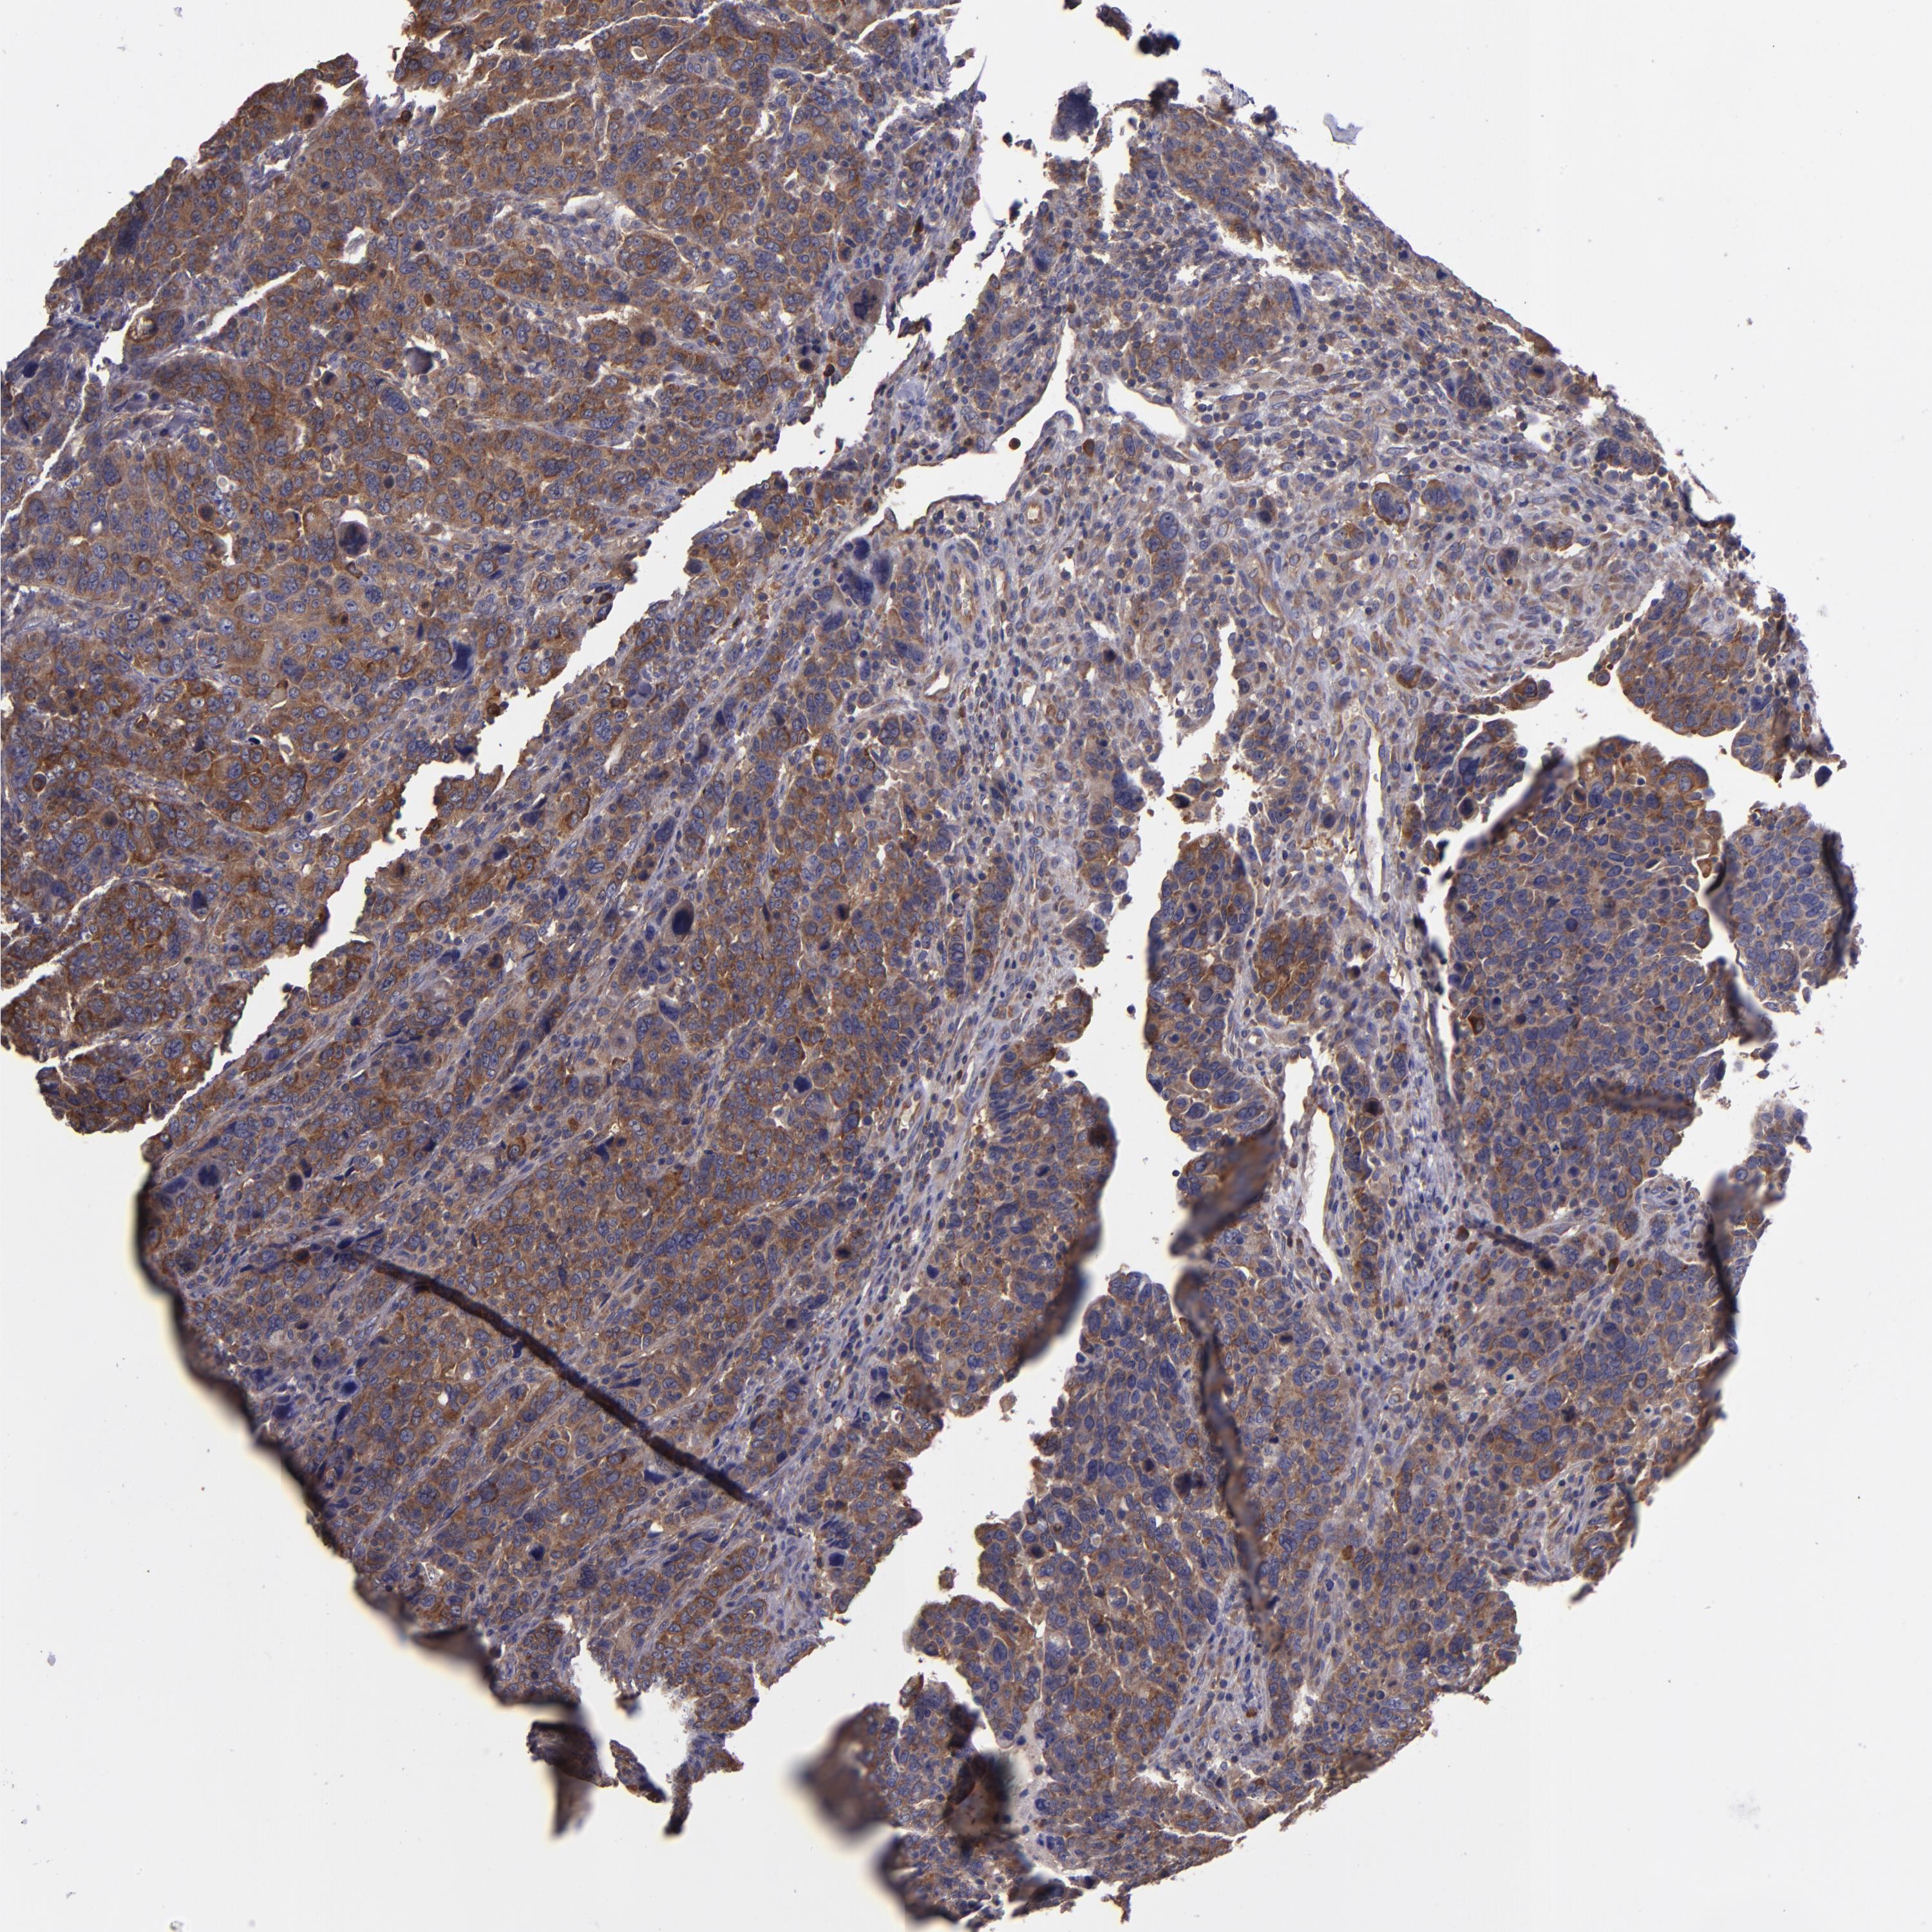

CANCER BREAST CANCER Show tissue menu

BRCA TCGA BRCA VALIDATION PROTEIN EXPRESSION